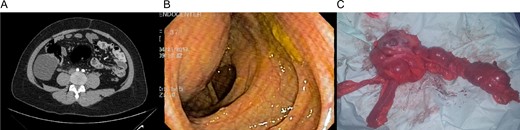

(A) CT revealing a 7 × 8 cm2 cystic lobulated mass dependent of the cecum wall. (B) Colonoscopy showing extrinsic compression of the lateral wall of the ascending colon. (C) Colonic mass and right colon.

The right colon with the mass was completely resected through a small midline incision without complications. The external surface of the mass was pinkish-gray color and the cystic wall was even in thickness ~0.4 cm (Fig. 1C) and contained clear mucous fluid. Pathology reported intestinal duplication cyst, microscopically, the cystic wall partially consisted of normal mucosa, submucosa, smooth muscle and serosa (Fig. 2A and B). No epithelial dysplasia or malignancy was evident.